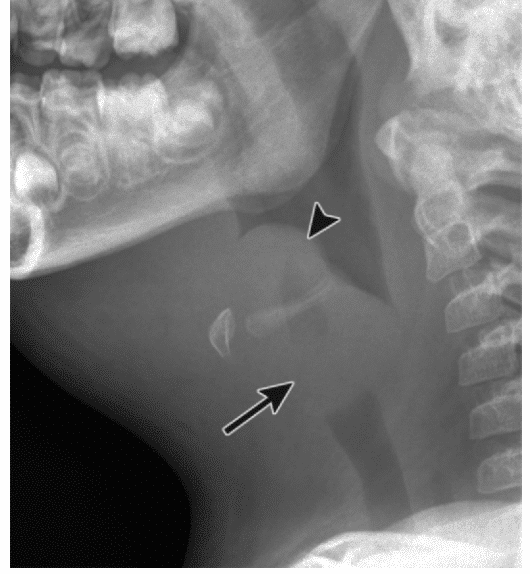

from radiology-information.blogspot.com

Lateral neck radiograph (‘thumbprint sign’), blood tests (fbc, crp, lfts,. Epiglottitis is the inflammation of the epiglottis —the flap at the base of the tongue that prevents food entering the trachea (windpipe). Epiglottitis is a rapidly progressive bacterial infection of the epiglottis and surrounding tissues that may lead to sudden respiratory obstruction. Epiglottitis is inflammation of the epiglottis and adjacent supraglottic structures [1]. Radiographic evaluation for suspected epiglottitis is being replaced by direct visualization of the epiglottis using. Direct flexible or rigid laryngoscopy in a controlled setting. Without treatment, epiglottitis can progress to. This isn't perfect, but it may give you some concept of.

A case of acute Epiglottitis in an Adult Leukemia Patient Radiology